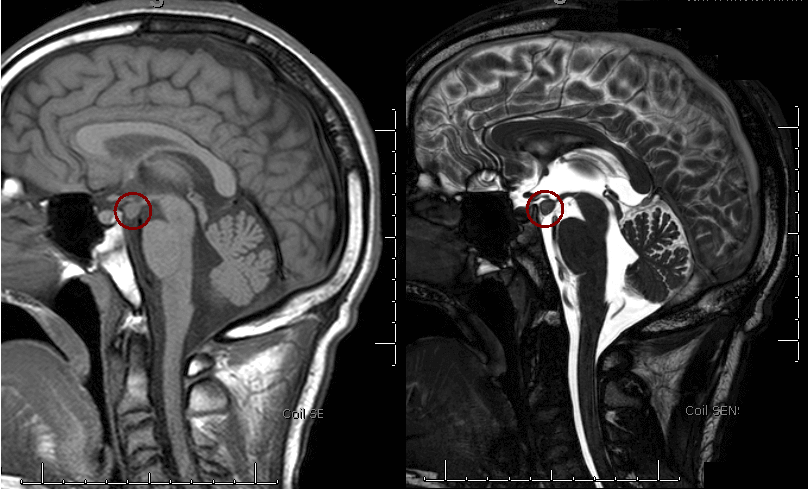

Hypothalamic Hemartoma and Gelastic Seizures

The MR images show an abnormal growth hanging down from the hypothalamus. This is a hypothalamic hemartoma, which in some cases can be a type of grey matter heterotopia within the tuber cinereum. It is usually a non-neoplastic congenital abnormality that can result in stereotypical seizures and behaviors.